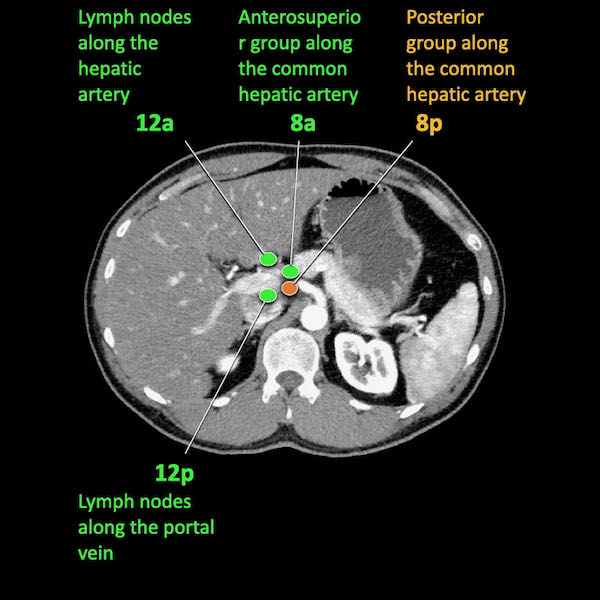

Điều quan trọng là phân biệt giữa hạch bạch huyết vùng và hạch bạch huyết ngoài vùng (di căn xa).

Các vị trí ngoài vùng chính là cạnh động mạch chủ và bên trái SMA.

Các hạch nghi ngờ ở những vị trí này cần được ghi nhận và sinh thiết.

Trong hình minh họa này, chúng tôi sử dụng các trạm hạch bạch huyết trong ung thư tụy theo đề xuất của Hội Tụy học Nhật Bản.

Danh sách đầy đủ được cung cấp trong chương về báo cáo. Nhấn vào đây.

Di căn hạch bạch huyết là yếu tố tiên lượng quan trọng và xảy ra ở khoảng hai phần ba bệnh nhân ung thư tụy có khả năng cắt bỏ.